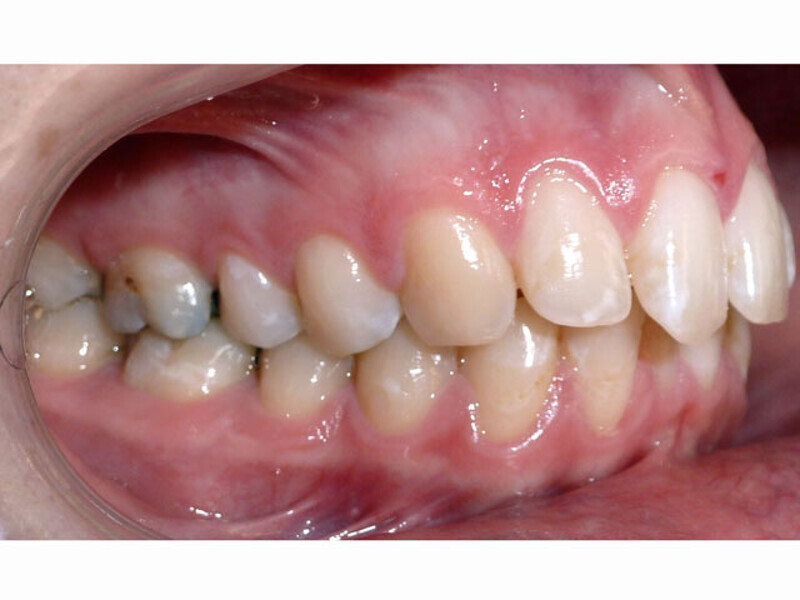

ClearCorrect treatment of crowding